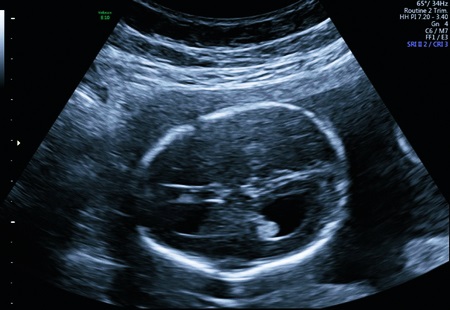

Анализ структур головного мозга у плода проводят во втором триместре, в период между 18 и 27 неделями беременности. В большинстве случаев патологические изменения обнаруживаются на плановом УЗИ. Диагноз также ставят на 30-33 недели беременности.

Проявления вентрикуломегалии зачастую не очевидны, и диагностика чаще всего происходит на УЗИ, где врач может заметить увеличение размеров боковых желудочков. Важно помнить, что не всегда это состояние приводит к серьезным последствиям, однако требует внимательного наблюдения.

Приобретенная вентрикуломегалия у новорожденного диагностируется при комплексном обследовании. Лабораторные анализы, инструментальные исследования делают в рамках дифференциальной диагностики. Болезнь нужно отличить от гидроцефалии.

Показатели УЗИ, МРТ, проведенных до родов и после, в 57-83% случаев существенно отличаются. Если у плода обнаружили расширение желудочков, не стоит паниковать. Для подтверждения или опровержения диагноза необходимо пройти повторное ультразвуковое и томографическое обследование новорожденного. Такие доводы представлены в издании «Частота и причины расхождений диагностических изображений у детей с вентрикуломегалией» G. M. Senapati, 2010.